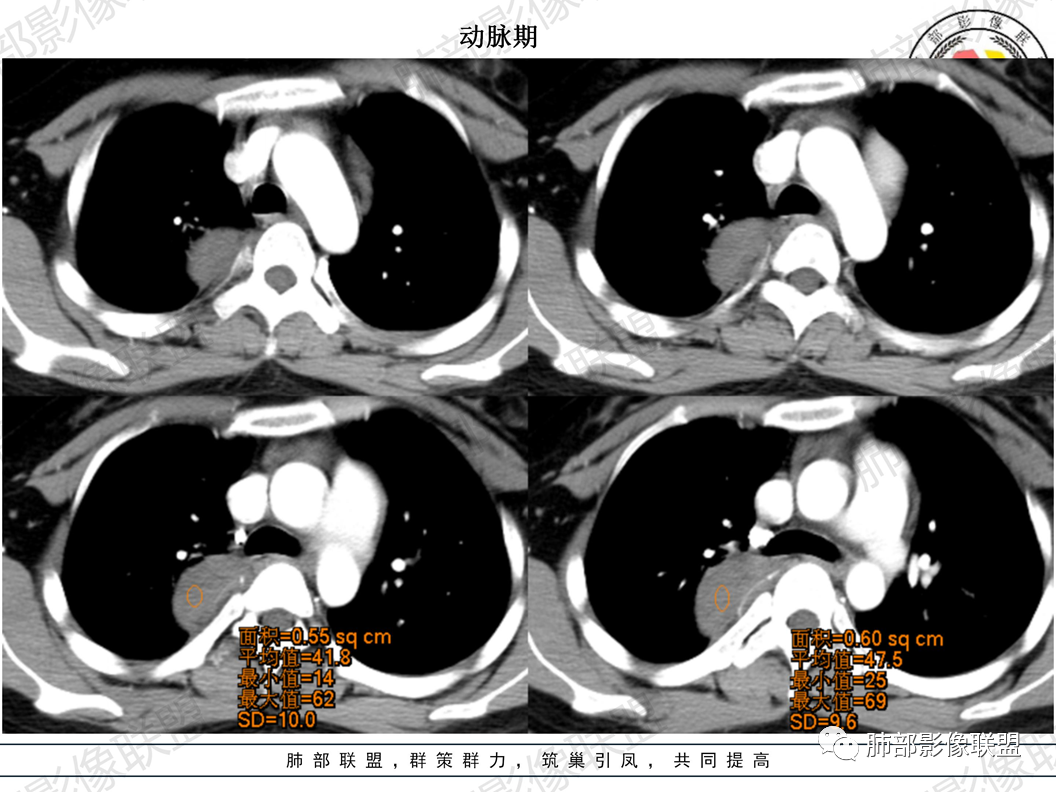

CT值平扫33HU,增强:45HU左右

定在轻度强化

5.轻度渐进性强化。

(3)增強:

后纵隔神经节细胞瘤常动脉期无明显強化、或轻度间隔、包膜或瘤体强化,延迟期可进一步斑片、结节状轻度或中度强化,强化程度进行增加,呈渐进性延迟强化,但強化程度一般为轻度到中度强化,究其原因可能是神经节细胞瘤瘤体内含有大量黏液基质和胶原纤维,使得细胞外间隙扩大,阻碍了对比剂的灌注,从而延缓了对比剂的积累,因此其动脉期多无明显强化或仅有轻度强化,延迟期呈渐进性轻度强化是后纵隔神经节细胞瘤强化特征。大部分病灶有轻度-中度强化,部分病灶无强化,这还可能与瘤组织内部间质血管含量多少相关,无强化病例瘤组织内部主要由胶质纤维和节细胞组成,间质血管较少,因此强化较低,而强化程度较高的病理可见较多的扩张、充血的毛细血管,引起较多的对比剂积蓄,因此强化相对明显。因此,神经节细胞瘤极少出现瘤组织早期强化,而多呈延长渐进性强化,增强扫描神经节细胞瘤内细胞成分可增强,黏液基质不强化。